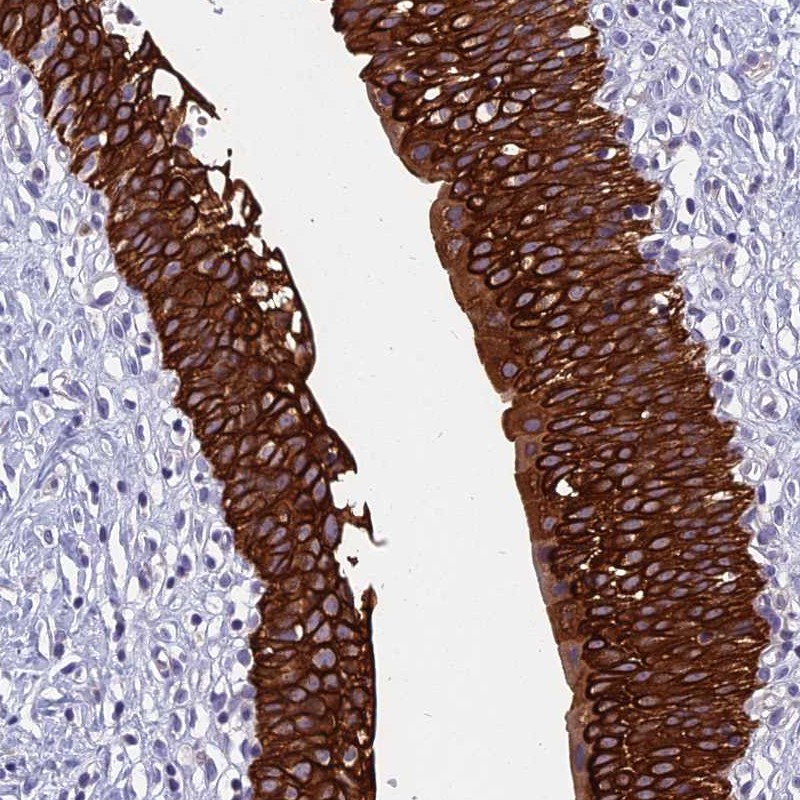

Immunohistochemical staining of human urinary bladder shows strong cytoplasmic and membranous positivity in urothelial cells.